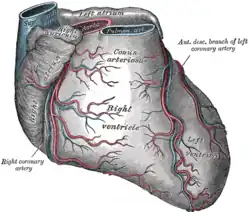

Coronary Arteries

Heart showing the Coronary Arteries The coronary circulation consists of the blood vessels that supply blood to, and remove blood from, the heart muscle itself. Although blood fills the chambers of the heart, the muscle tissue of the heart, or myocardium, is so thick that it requires coronary blood vessels to deliver blood deep into the myocardium. The vessels that supply blood high in oxygen to the myocardium are known as coronary arteries. The vessels that remove the deoxygenated blood from the heart muscle are known as cardiac veins. The coronary arteries that run on the surface of the heart are called epicardial coronary arteries. These arteries, when healthy, are capable of auto regulation to maintain coronary blood flow at levels appropriate to the needs of the heart muscle. These relatively narrow vessels are commonly affected by atherosclerosis and can become blocked, causing angina or a heart attack. The coronary arteries are classified as "end circulation", since they represent the only source of blood supply to the myocardium: there is very little redundant blood supply, which is why blockage of these vessels can be so critical. In general there are two main coronary arteries, the left and right. • Right coronary artery • Left coronary artery Both of these arteries originate from the beginning (root) of the aorta, immediately above the aortic valve. As discussed below, the left coronary artery originates from the left aortic sinus, while the right coronary artery originates from the right aortic sinus. Four percent of people have a third, the posterior coronary artery. In rare cases, a patient will have one coronary artery that runs around the root of the aorta.